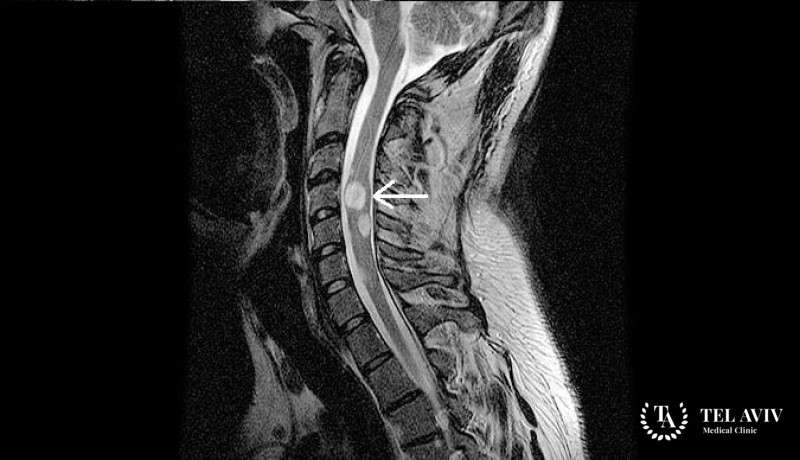

Основные методы диагностики и лечения астроцитомы

Комплексное обследование включает ряд процедур, которые помогут определиться с диагнозом и в соответствии со всеми факторами – наиболее адекватным лечением.

- МРТ.